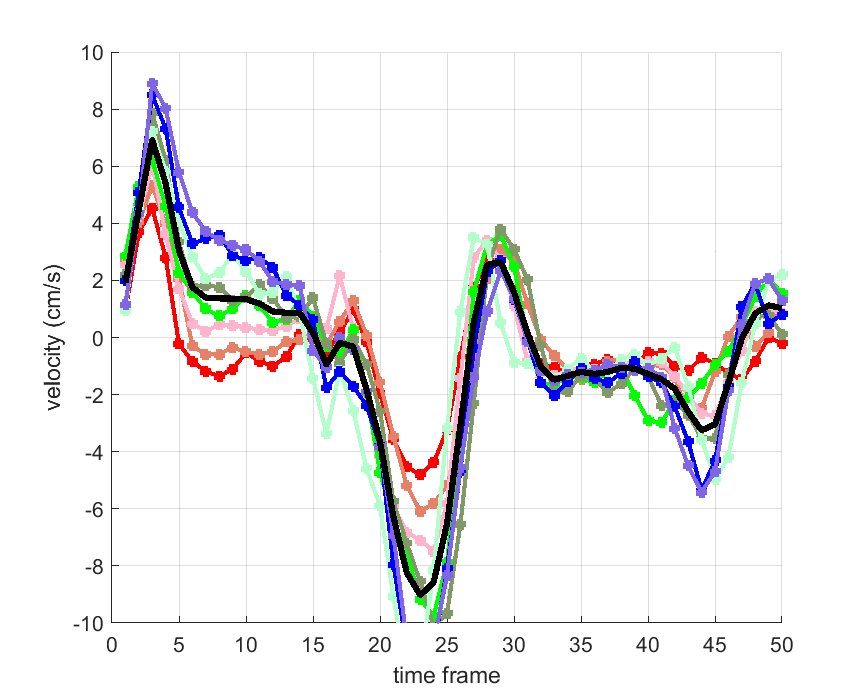

Time courses of the estimated translational component per subject, frame, slice and volume along the 3 velocity directions x, y and z are presented in Fig.6 - Fig.8.